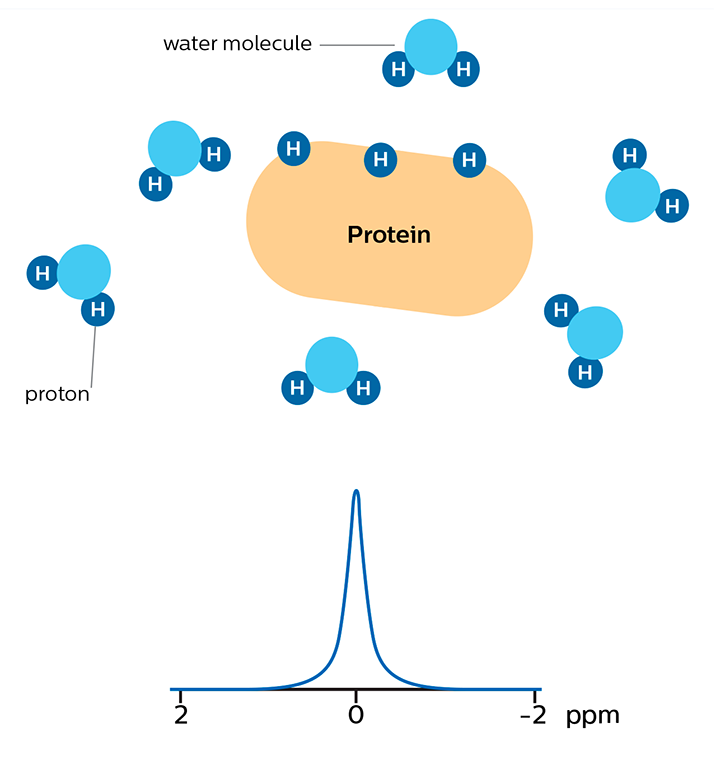

In APT weighted imaging and other CEST methods, the MRI signal is generated by a mechanism different from that of basic MRI. These CEST techniques are based on the chemical exchange of hydrogen atoms. The signal of amide protons of peptide bonds in proteins is too low to be measured in normal MRI. The hydrogen (proton) exchange between protein amide groups and surrounding water allows a different way to measure these amide protons. In APT a narrow RF prepulse (saturation pulse) at the amide hydrogen’s frequency is given to attenuate its MR signal. Because the amide group and water continually exchange hydrogen atoms, the number of saturated protons will build up in water, so that the measured water signal will become lower. The change of the MRI signal of water provides an indirect way to measure the presence of amide. APT images are usually presented as color maps, created by using an asymmetry calculation so that presence of APT is shown as a positive colored signal.

Proteins with amide protons surrounded by water molecules that are moving around.

MR signal of water is high